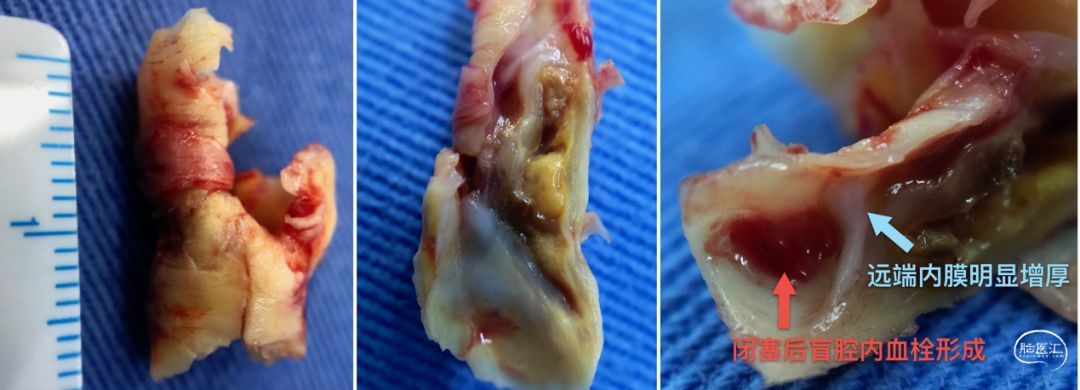

再来看看斑块,其实很局限,从剖面来看,的确是闭塞了,而且时间不短,远端内膜已经明显增厚。闭塞远端的盲腔扩大,并有明显的新鲜血栓形成,这样的逆行血流在盲腔明显变慢并长期滞留(如吲哚氰绿荧光造影所示)从而形成血栓,并被冲刷导致脱落,这有点类似Carotid Web那样的逆向血流机理。这同时也解释了手术准备时出现的“异象”,画切口就脱落了8个栓子,消毒7个,切开皮肤还掉了5个栓子,我有那么不小心吗?![]()